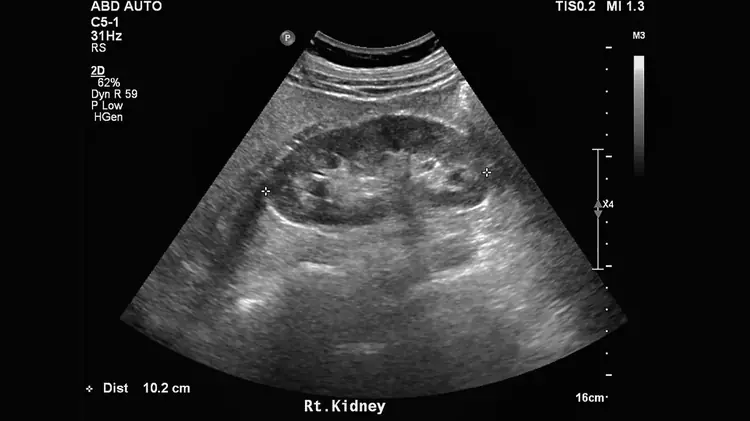

Du calcul Ă lâobstruction : trier le bĂ©nin du grave